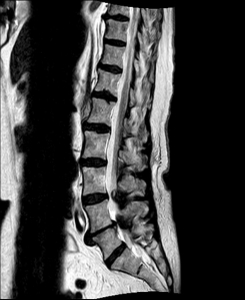

Spinalkanalstenose I

MRI with lateral reconstruction of the lumbar spine. The hourglass-like narrowing of the spinal canal can be seen at two heights.